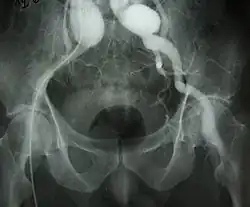

Tętniak prawdziwy (łac. aneurysma verum; ang. true aneurysm) – workowate poszerzenie światła naczynia, przy zachowaniu ciągłości ścian o pierwotnej budowie. Związany z wrodzonym defektem budowy ściany tętnicy (np. zespół Marfana) lub powstały na skutek jej osłabienia przez proces zapalny. Może być skutkiem urazu. Występuje w większości tętnic. Leczenie polega zazwyczaj na wycięciu i wstawieniu protezy naczyniowej. W przypadku naczyń mózgowych leczenie polega, jeżeli to możliwe, na zaklipsowaniu tętniaka. W innych mniejszych naczyniach pozostawia się je bez leczenia. Tętniaki prawdziwe aorty o średnicy poniżej 4 cm nie podlegają leczeniu. Tętniaki większe leczone są tylko w przypadkach zagrażających pęknięciem (np. szybko poszerzający się tętniak).